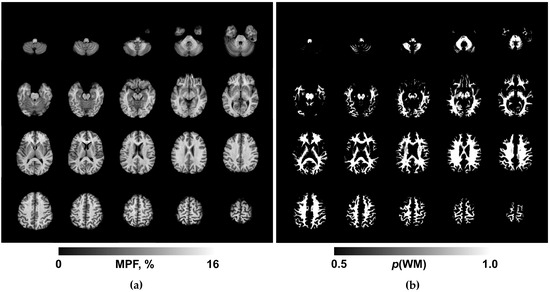

Macromolecular Proton Fraction Reveals Divergent White Matter Myelination in Bipolar Disorder and Unipolar Recurrent Depression

by Sofia Gusakova, Liudmila Smirnova, Oleg Borodin, Elena Epimakhova, Alexander Seregin and Vasily Yarnykh

Bioengineering 2026, 13(1), 78; https://doi.org/10.3390/bioengineering13010078 - 11 Jan 2026

Recurrent depressive disorder (RDD) and bipolar disorder (BD) are the most common affective disorders worldwide. However, the pathogenesis of these disorders remains far from understood. Macromolecular proton fraction (MPF) mapping is a sensitive and specific quantitative MRI method for the assessment of brain [...] Read more.

Recurrent depressive disorder (RDD) and bipolar disorder (BD) are the most common affective disorders worldwide. However, the pathogenesis of these disorders remains far from understood. Macromolecular proton fraction (MPF) mapping is a sensitive and specific quantitative MRI method for the assessment of brain tissue myelination, but its clinical value for affective disorders remains unknown. This cross-sectional study employed fast MPF mapping on a 1.5 T MRI scanner using the single-point synthetic reference method to investigate myelin abnormalities in white matter of RDD and BD patients. ANOVA revealed a significant main effect of the group (RDD vs. BD vs. two age-matched control groups; F (3.76) = 7.42, p < 0.001, η2 = 0.227). MPF values were significantly reduced in RDD versus BD patients (p < 0.001). BD showed elevated MPF compared to controls (p = 0.01). MPF levels showed significant weak-to-moderate correlations with clinical scales of affective disorders. These findings demonstrate divergent cerebral myelination patterns—hypomyelination in RDD versus an increased myelin content in BD. In conclusion, MPF mapping demonstrated a promise as a marker of myelin content changes in affective disorder. Full article